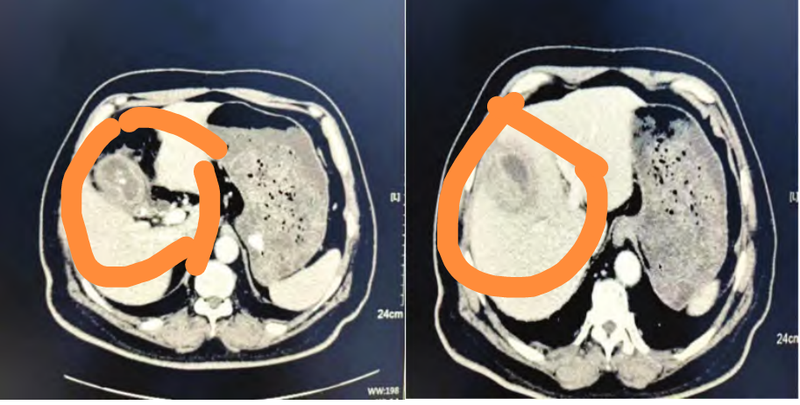

CT 檢查診斷膽囊腺肌癥的典型病例

1、患者,男性,58歲,CT掃描可見(jiàn):膽囊壁增厚,增強(qiáng)掃描明顯延遲強(qiáng)化,膽囊底見(jiàn)囊性低密度,呈串珠狀,鄰近肝臟見(jiàn)片狀低密度,增強(qiáng)掃描延遲強(qiáng)化,膽囊內(nèi)壁光滑,其內(nèi)見(jiàn)多發(fā)點(diǎn)狀高密度。最終診斷結(jié)果:膽囊腺肌癥并鄰近肝臟炎性浸潤(rùn),膽囊多發(fā)結(jié)石。見(jiàn)圖1.2、患者,女性,60歲,CT掃描可見(jiàn):膽囊底壁增厚,邊緣毛糙,增強(qiáng)掃描明顯強(qiáng)化,見(jiàn)多個(gè)囊性低密度灶,邊界清楚,膽囊內(nèi)壁光整。最終診斷結(jié)果為膽囊腺肌癥。見(jiàn)圖2.本文選自:宮凱等,CT檢查診斷膽囊腺肌癥的臨床意義研究。原文鏈接地址:CT檢查診斷膽囊腺肌癥的臨床意義研究-中國(guó)知網(wǎng)(cnki.net)